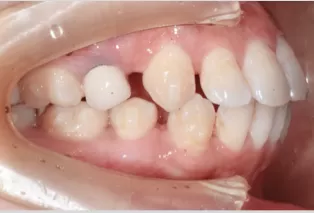

Photos intra-orales